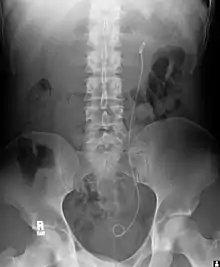

| Ureteral stents are used to ensure the patency of a ureter, which may be compromised, for example, by a kidney stone. This method is sometimes used as a temporary measure to prevent damage to a blocked kidney until a procedure to remove the stone can be performed. | ![]() Example of a ureteral stent used to alleviate hydronephrosis of the kidney |

| Prostatic stents are placed from the bladder through the prostatic and penile urethra to allow drainage of the bladder through the penis. This is sometimes required in benign prostatic hypertrophy. | ![]() Example of a stent/catheter used in the prostate to treat an enlarged prostate and provide relief in cases of obstructed urination |